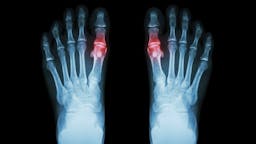

¿Tienen cabida los almidones en las dietas cetogénicas? ¿Podemos culpar a la cetosis del rebrote de gota?

| Cardiopatía (14) | Gota (2) | Trastorno bipolar (8) |